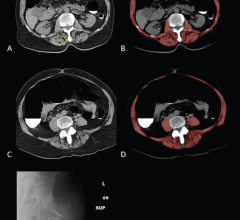

May 1, 2023 — Artificial intelligence (AI) could help doctors diagnose lung cancer earlier, according to a study led by ...